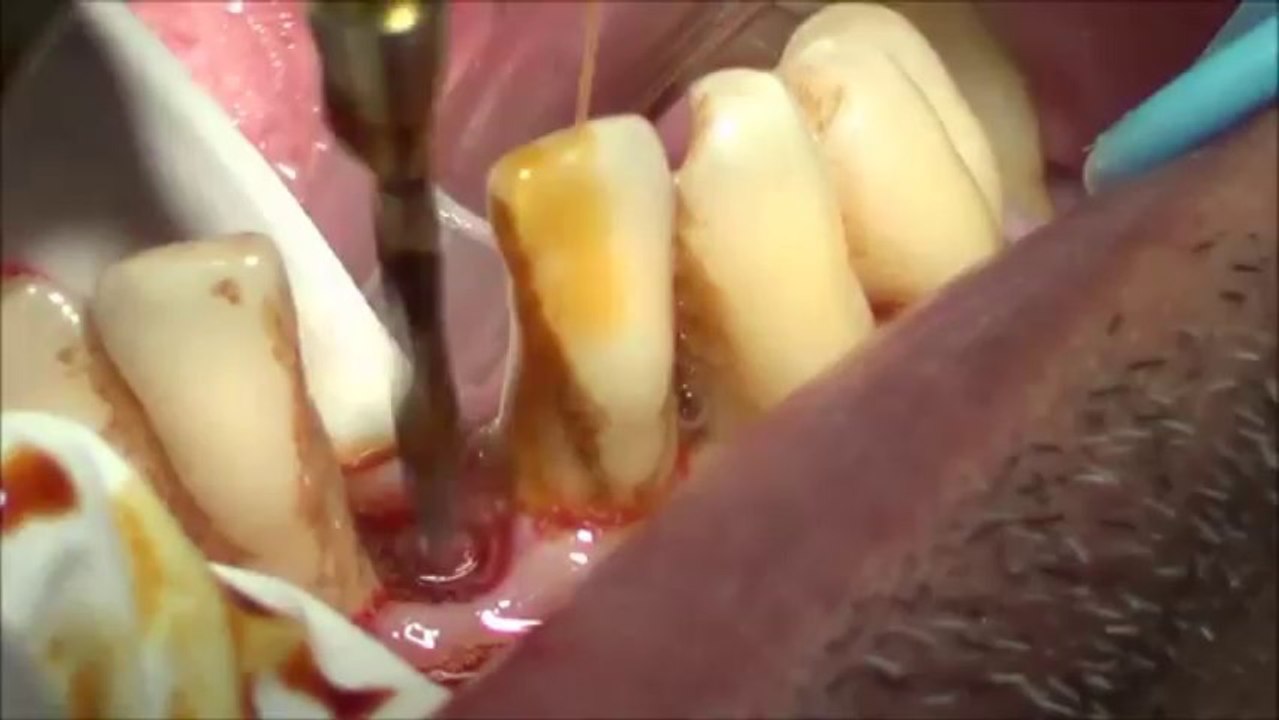

Dental Implant - Real Time Computer Guided Implant Placement - IGI Webinar